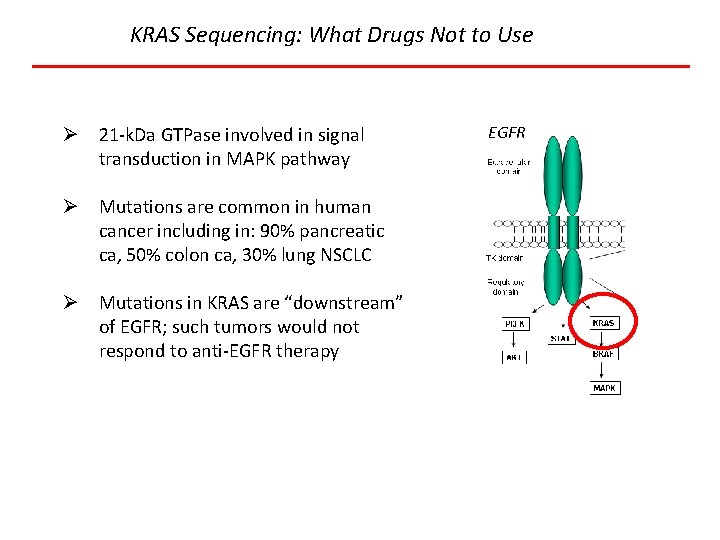

KRAS Sequencing: What Drugs Not to Use Ø 21 -k. Da GTPase involved in signal transduction in MAPK pathway Ø Mutations are common in human cancer including in: 90% pancreatic ca, 50% colon ca, 30% lung NSCLC Ø Mutations in KRAS are “downstream” of EGFR; such tumors would not respond to anti-EGFR therapy EGFR